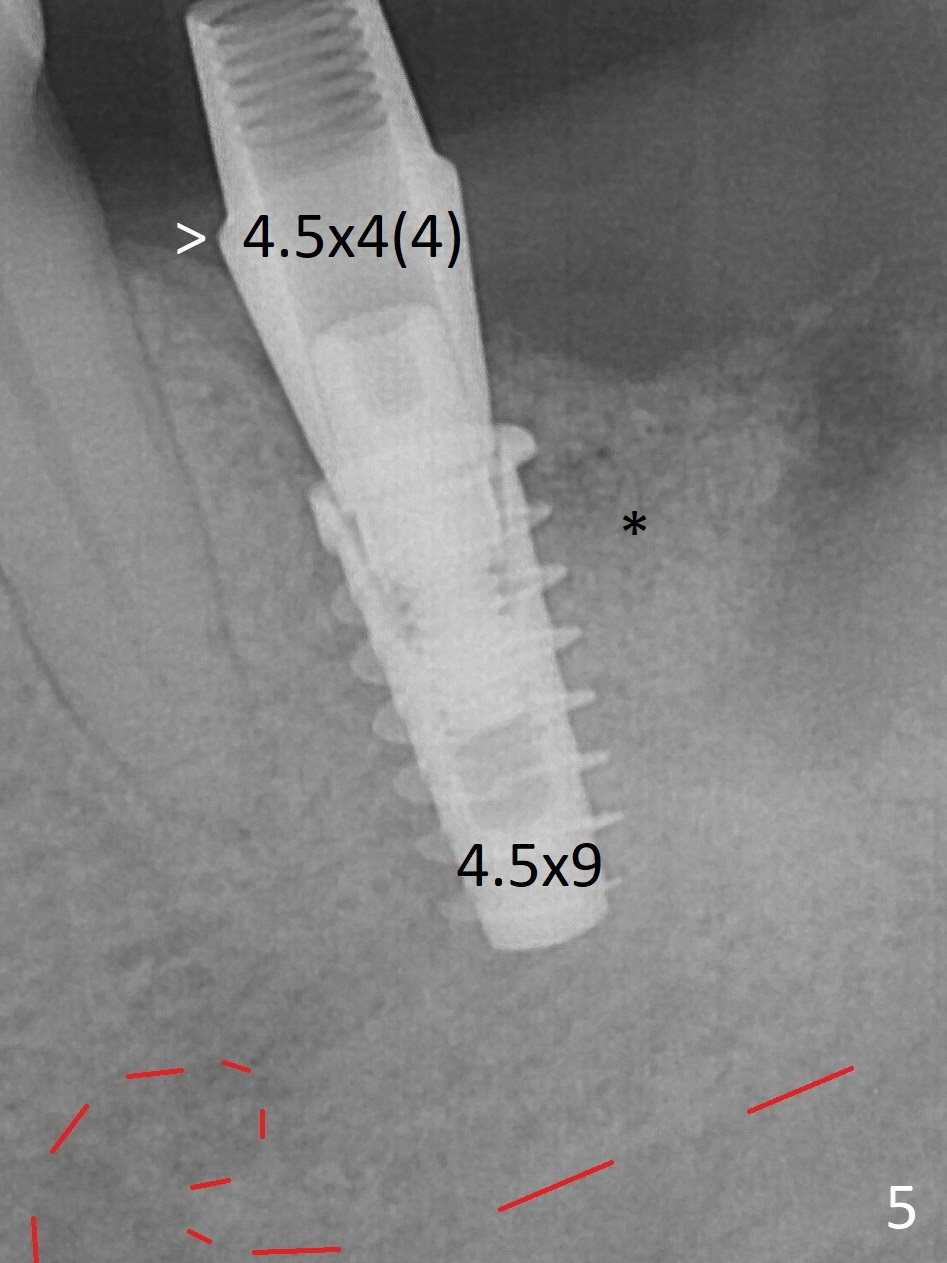

When the patient returns for treatment, the implant at #19 is mobile with tenderness (without purulence, Fig.1). She finally agrees to have CT taken (Fig.2,3 (coronal section (L: lingual))). The implant is removed after several carpules of cocktail anesthetics for infiltration and one carpule for block. Osteotomy is initiated in the mesial slope of the defect (Fig.2,4). The advantage of immediate implant re-placement is wide bone at the intended area (Fig.3). After change in trajectory (compare Fig.4 (4x11 mm dummy implant) and Fig.5), a 4.5x9 mm IBS implant is placed with insertion torque of 50 Ncm (Fig.5); with Osteogen plug placed in the distal defect, allograft (*) is placed immediately distal to the implant. With the longest cuff available (4 mm), the margin of the abutment (4.5x4(4) mm) is equi-crestal (>). When the 9 mm long implant is placed deep, the coronal threads of the implant are distally exposed (Fig.6 between arrowheads) less than those of the 11 mm one placed superficial (Fig.2). Intraoperative socket hemorrhage is controlled by packing gauze saturated with Epinephrine 1:50,000. The patient chooses not to take Medrol Dose Pack for postoperative edema. She removes periodontal dressing herself prematurely. The socket wound dehiscence is noted the first postop visit (7th day). Fig.7 is taken 9 days postop before re-suturing. The patient insists on removing the implant with dull pain. Three months 10 days postop, she returns with loss of the abutment and a fistula (Fig.8). In fact there is bone formation distal to the implant. Torque wrench has to used to remove the implant.